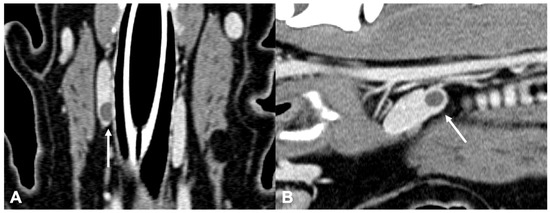

Figure 3.

CT appearance of parathyroid gland adenoma. Post-contrast dorsal CT reconstruction in two dogs with parathyroid gland adenoma (arrow) at the level of the right external parathyroid. Note the rounded (A) and ovoid (B) shape; in both cases the parathyroid adenoma is hypoattenuating with respect to the thyroid tissue and homogenously enhancing.